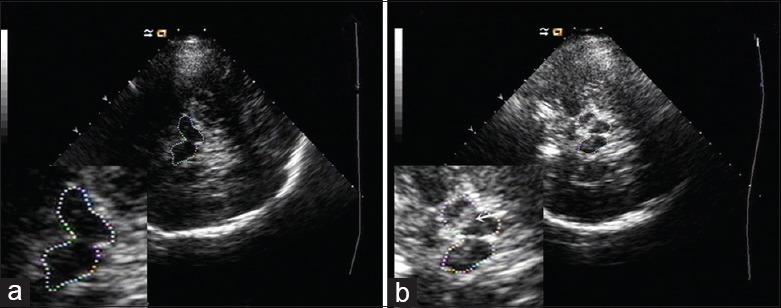

Numerous studies have demonstrated that patients with Parkinson's disease (PD) have a higher prevalence of substantia nigra (SN) hyperechogenicity compared with controls. Our aim was to explore the neuroimaging characteristics of transcranial sonography (TCS) of patients with PD and those with PD with dementia (PDD). The correlation between the echogenicity of the SN and clinical symptoms in Chinese patients with PDD was also assessed.

The ratios of SN hyperechogenicity (SN+), maximum sizes of SN+, and widths of third ventricle (TV) were measured using TCS for all the recruited patients. Data were analyzed using one-way analysis of variance, rank-sum test, Chi-square test, and receiver-operating characteristic (ROC) curve analysis.

The final statistical analysis included 46 PDD patients, 52 PD patients, and 40 controls. There were no significant differences in ratios of SN+ and maximum sizes of SN+ between PDD and PD groups (P > 0.05). TV widths were significantly larger in PDD group (7.1 ± 1.9 mm) than in PD group (6.0 ± 2.0 mm) and controls (5.9 ± 1.5 mm, P < 0.05); however, the ratios of enlarged TV did not differ among the three groups (P = 0.059). When cutoff value was set at 6.8 mm, the TV width had a relatively high sensitivity and specificity in discriminating between PDD and PD groups (P = 0.030) and between PDD group and controls (P = 0.003), based on ROC curve analysis. In PDD patients, SN+ was more frequently detected in akinetic-rigid subgroup, and patients with SN+ showed significantly higher Hoehn and Yahr stage and Nonmotor Symptoms Questionnaire scores (P < 0.05).

Compared to Chinese patients with PD, patients with PDD had a wider TV, altered SN sonographic features, and more severe clinical symptoms. Our findings suggest that TCS can be used to assess brain atrophy in PD and may be useful in discriminating between PD with and without dementia.

大量研究表明,帕金森病(PD)患者的黑质(SN)回声增强发生率高于对照组。我们的目的是探讨中国 PD 患者和 PD 合并痴呆(PDD)患者经颅超声(TCS)的神经影像学特征。还评估了 PDD 患者 SN 回声强度与临床症状之间的相关性。

使用 TCS 测量所有入组患者的 SN 回声增强比(SN+)、SN+最大尺寸和第三脑室(TV)宽度。采用单因素方差分析、秩和检验、卡方检验和受试者工作特征(ROC)曲线分析进行数据分析。

最终的统计分析纳入了 46 例 PDD 患者、52 例 PD 患者和 40 例对照组。PDD 组与 PD 组 SN+比和 SN+最大尺寸无显著差异(P>0.05)。PDD 组 TV 宽度明显大于 PD 组(7.1±1.9mm)和对照组(5.9±1.5mm,P<0.05),但三组间扩大的 TV 比无差异(P=0.059)。当截断值设为 6.8mm 时,根据 ROC 曲线分析,TV 宽度在区分 PDD 与 PD 组(P=0.030)和 PDD 与对照组(P=0.003)方面具有较高的敏感性和特异性。在 PDD 患者中,运动不能僵硬亚组更常检测到 SN+,且 SN+患者的 Hoehn 和 Yahr 分期和非运动症状问卷评分显著更高(P<0.05)。

与中国 PD 患者相比,PDD 患者的 TV 更宽,SN 超声特征改变,且临床症状更严重。我们的研究结果表明,TCS 可用于评估 PD 患者的脑萎缩,有助于区分 PD 伴或不伴痴呆。